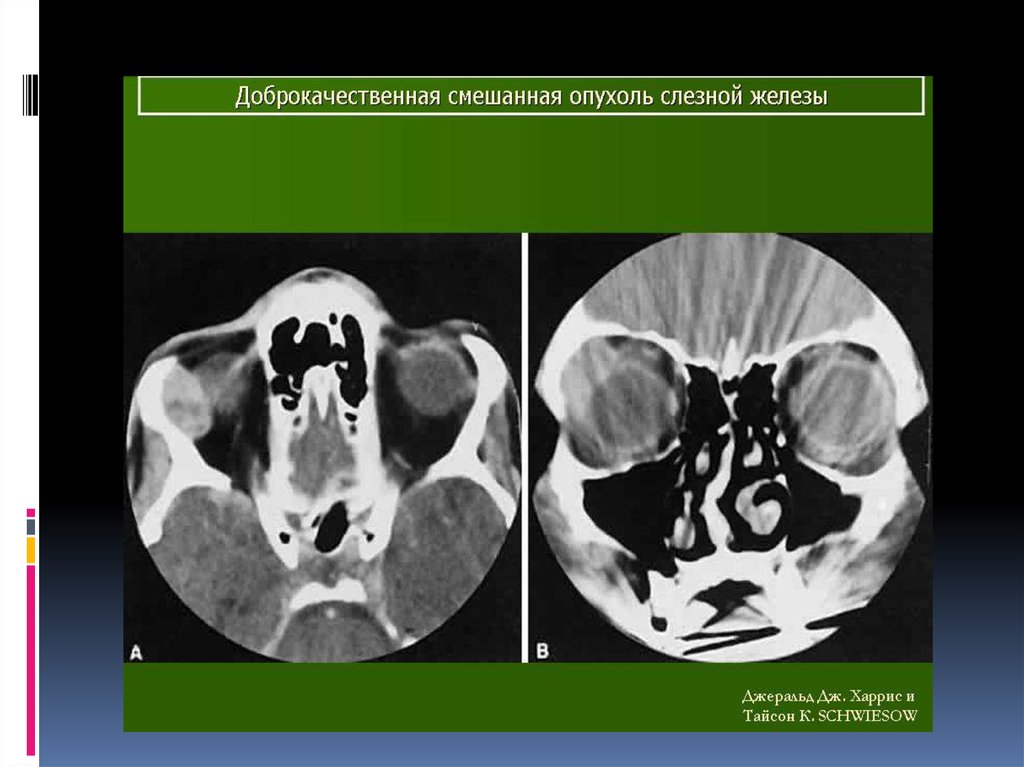

Диагностика. Rg - выявляют увеличение орбиты в

размерах за счет истончения и смещения кверху и

кнаружи ее стенки в области слезной ямки.

УЗ - сканирование позволяет визуализировать

тень плотной опухоли, окруженную капсулой и

деформацию глаза.

При КТ опухоль визуализируется более четко,

можно проследить целость капсулы,

распространенность опухоли в орбите, состояние

прилежащих костных стенок орбиты.